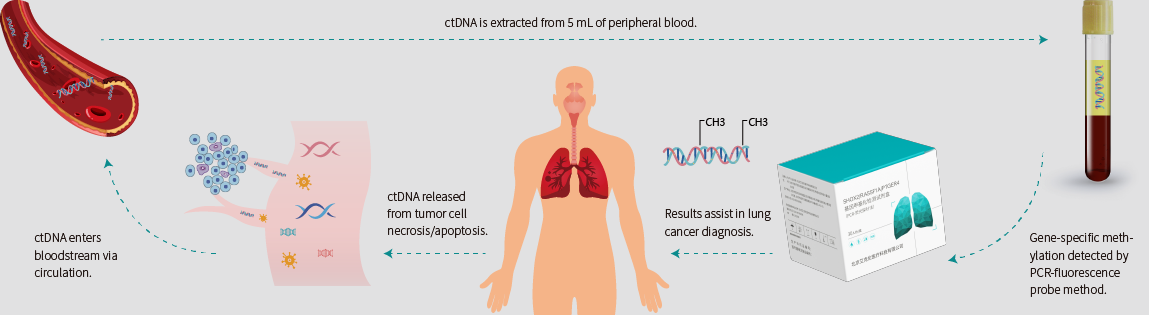

A single blood sample reveals traces of the tumor

After the tumor cells carrying genetic information and epigenetic alterations undergo necrosis or apoptosis, they release fragmented genomic DNA into the peripheral blood, which is known as circulating tumor DNA (ctDNA).[2]By capturing these trace amounts of ctDNA and detecting the specific changes in tumor methylation sites, this method can provide earlier and more accurate information on the occurrence and development of tumors compared to traditional detection techniques.[3]